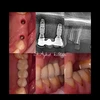

فقدان الأسنان

التهاب الغشاء المخاطي حول الزرعة

التهاب أنسجة ما حول الزرعة

مجالات التخصص

طبيب أسنان